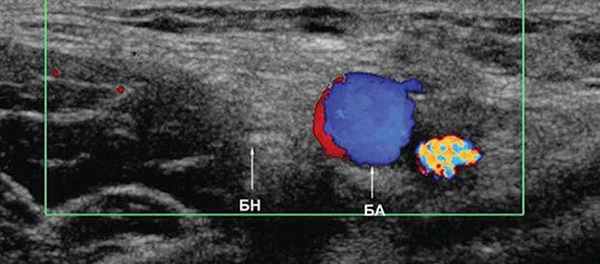

УЗИ бедренного нерва проводили в положении пациента лежа на спине. Бедренный нерв визуализировали в паховой области латеральнее сосудистого пучка от уровня паховой связки до верхней трети бедра (рис. 2, 3). Исследование проводили в поперечной и продольной плоскостях сканирования (рис. 2, 4).

Рис. 3. Режим ЦДК. Исследование правого бедренного нерва в поперечной плоскости сканирования на уровне паховой области: БН - бедренный нерв, БА - бедренная артерия.